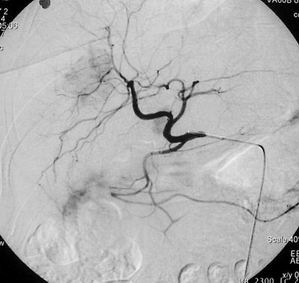

Obrázek 2 - angiografie a. hepatica před léčbou s patrnými hypervakularizovanými ložisky, které odpovídají metastázám

V první fázi výkonu provádíme přehlednou diagnostickou angiografii abdominální aorty a selektivní nástřik renální tepny k posouzení cévního zásobení postižené ledviny (časté jsou varianty v počtu zásobujících tepen).